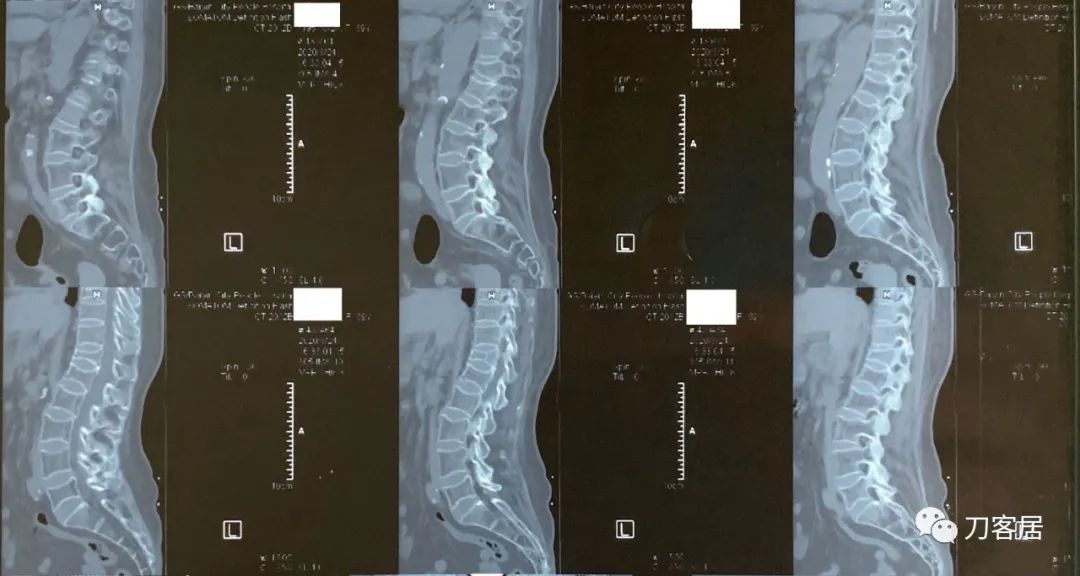

图08-20200824白银市人民医院腰椎CT

图09-20200824白银市人民医院腰椎CT